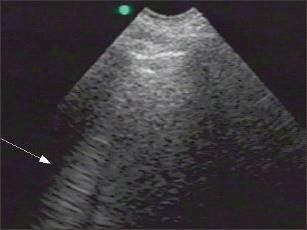

Figure 4 –

This split-screen display of pleural ultrasonography includes the normal display (top) and M-mode display with "seashore sign" (bottom).